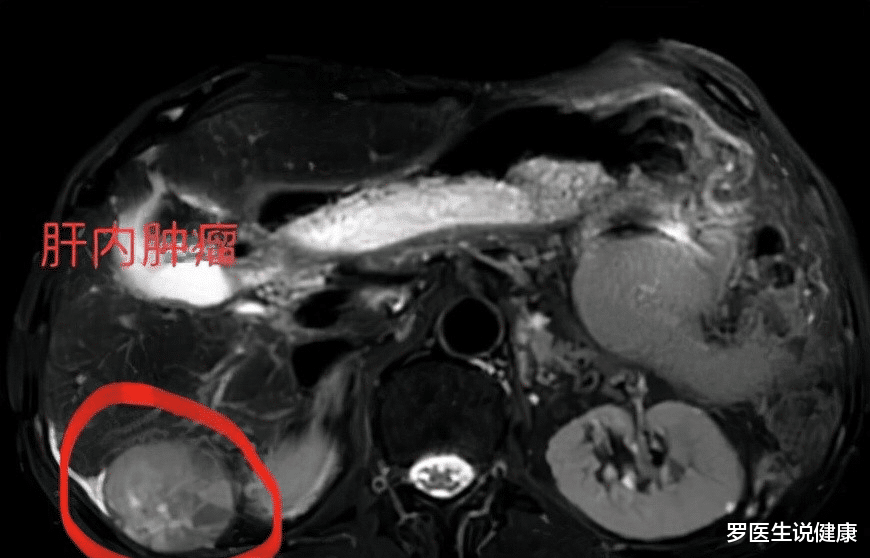

医生看完秦先生的体检结果以后 , 问秦先生以前有没有乙肝啥的 。 秦先生非常肯定地说没有 , 但是他后面又说了一句话 , 让医生非常的警惕 。 他说:小时候得过肝炎 , 但是那时候就治好了 。

医生没有多说话 , 给秦先生开了乙肝五项、肝功能、甲胎蛋白、增强核磁去检查 。 等到秦先生和女儿正准备走出诊室的时候 , 医生突然叫住了小秦 , 说到:家属你留一下 , 跟你说一下一会检查的注意事项 。 并跟秦先生说到:你先去窗口缴费吧 。 医生跟留下来的小秦说到:你爸爸的病有可能是肝癌 , 等结果出来以后我当着他的面说真实病情 , 到时候你知道就行 。 小秦感激地点了点头 , 赶紧出去陪着秦先生去做检查了 。

折腾了大半天 , 终于这些检查都做完了 。 等到下午结果都出来了 , 便拿着检查结果去找医生复诊 。 小秦看到还是上午的那个医生 , 突然放心了下来 , 她让爸爸坐在了医生对面的椅子上 , 她站在旁边静静的看者医生在电脑上浏览着爸爸的检查结果 。